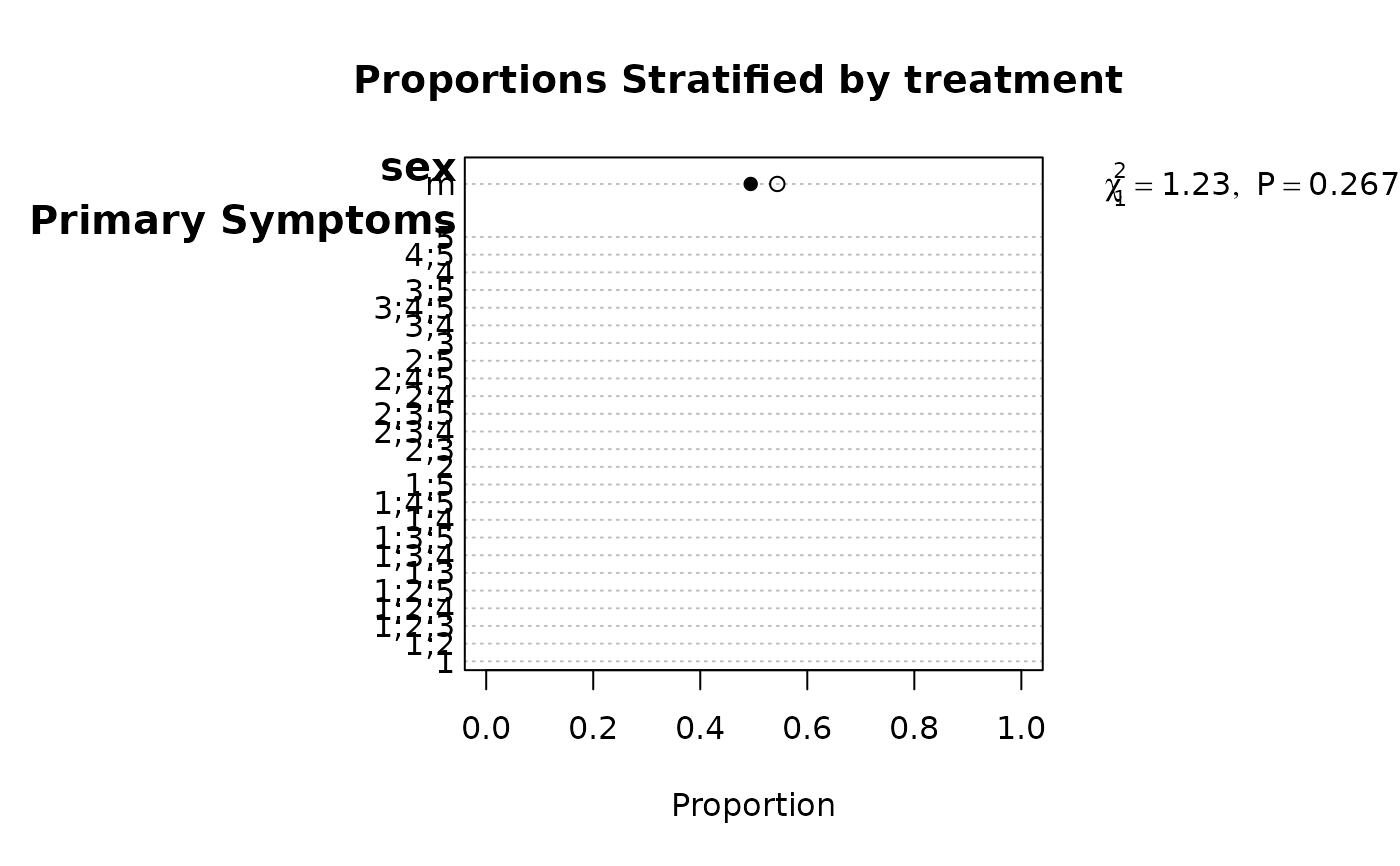

f <- summaryM(age + sex + sbp + Symptoms ~ treatment, test=TRUE)

#> |sex : m |500| 0.49 (129) | 0.54 (130) |Chi-square=1.23 d.f.=1 P=0.267|

plot(f) # first specify options(grType='plotly') to use plotly

plot(f, conType='dot', prtest='P')